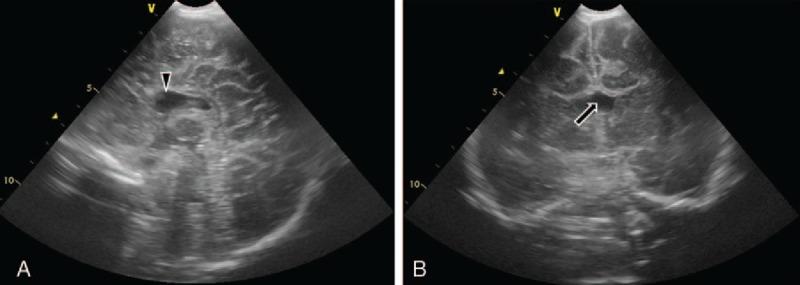

Septo-optic dysplasia (SOD) is a rare congenital disorder that may cause jaundice in infants. However, it is usually prone to neglect and misdiagnosis in infants with cholestasis because endocrine disorder such as panhypopituitarism is rare in the cause of infantile cholestasis. We report a case of SOD concurrent with acquired cytomegalovirus (CMV) infection, who presented with prolonged jaundice as the first clinical sign.

The patient was a 2-month-old male infant who presented with cholestasis, combined with fever and panhypopituitarism.

He was diagnosed with SOD and acquired CMV infection.

视隔发育不良(SOD)是一种罕见的先天性疾病,可能导致婴儿黄疸。然而,在胆汁淤积的婴儿中,它通常容易被忽视和误诊,因为在婴儿胆汁淤积的病因中,全垂体功能减退等内分泌紊乱很少见。我们报告一例SOD并发获得性巨细胞病毒(CMV)感染的病例,该病例以长期黄疸作为首发临床症状。

该患者为一名2个月大的男婴,表现为胆汁淤积,并伴有发热和全垂体功能减退。

他被诊断为视隔发育不良和获得性巨细胞病毒感染。